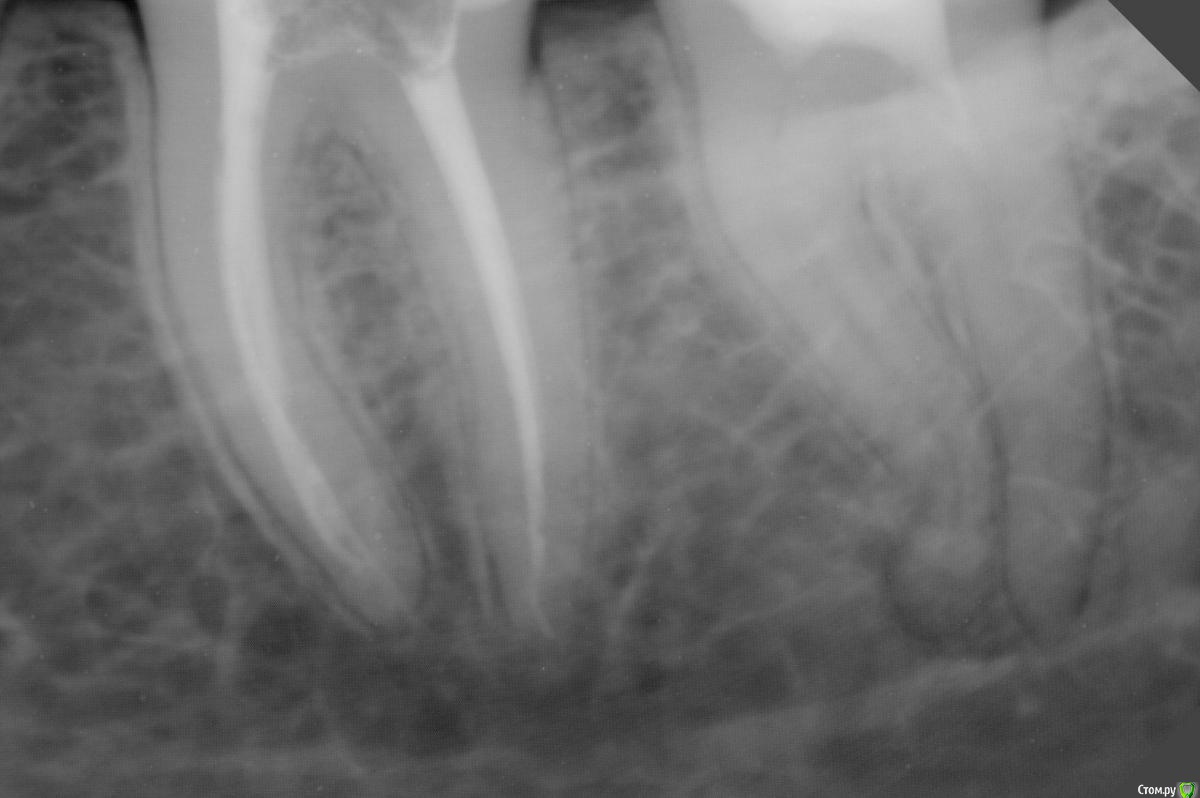

dr.Dre Опубликовано 7 августа, 2019 Поделиться Опубликовано 7 августа, 2019 Добрый день .Коллеги подскажите пожалуйста протокол работы с таким каналом?22 зуб Ссылка на комментарий

Kolchanov Опубликовано 7 августа, 2019 Поделиться Опубликовано 7 августа, 2019 Краун, до изгиба чем угодно, за изгиб что-то тоненькое и гибкое. Типа профайла 25.04. Но, даже если заступените криминала не будет. Плотно подогнанной гуттаперчиной активировать растворы полчасика и нормально будет. 2 Ссылка на комментарий

Kolchanov Опубликовано 8 августа, 2019 Поделиться Опубликовано 8 августа, 2019 Профайлы отлично берут изгибы. Главное - новые файлы и не торопиться. http://forum.stom.ru/topic/20766-materialy-dlia-edodontii/?view=findpost&p=321250 Ссылка на комментарий

St. Опубликовано 10 августа, 2019 Поделиться Опубликовано 10 августа, 2019 Пациентка недавно приходила с жалобами на боль при жевании в 37 зубе. Я отправила ее к другому специалисту, т.к. не уверена, что у меня есть что-то настолько гибкое. А чем лучше проходить такой канал по вашему мнению?а еще лучше что нибудь из сплава с памятью формы(хайфлекс. соко или что то подобное) Ссылка на комментарий